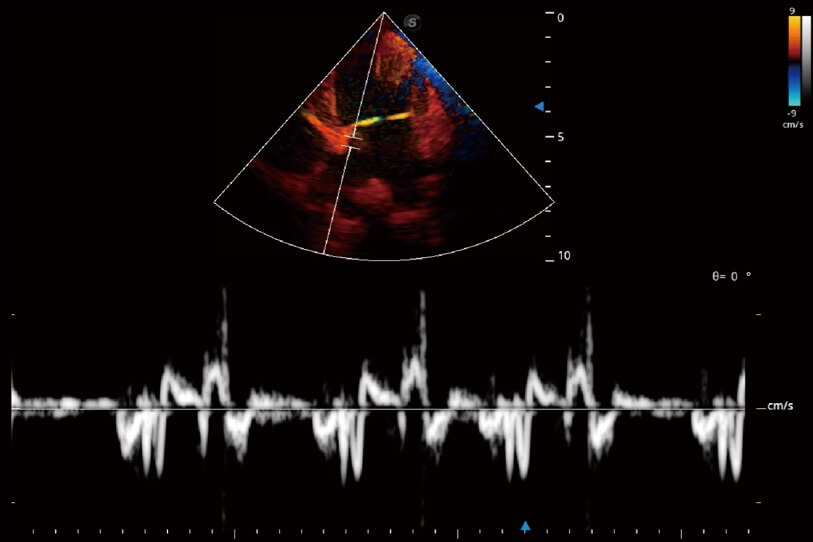

通过360度任意调节3条M型取样线,在同一心动周期上观察心脏不同位置的运动曲线,得到准确的心功能测量数据,有效评估心肌运动及左心室功能。

实时用颜色表示心肌组织运动,观察和定量组织的运动情况,对快速检测与评估心肌的灌注和活性、电传导及心肌收缩和舒张功能等均能提供重要的诊断信息。